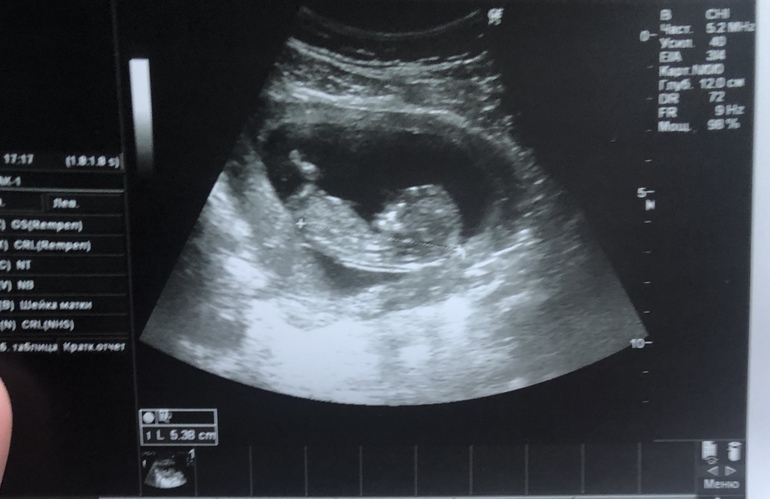

Вот на первом скрининге вид снизу, сбоку не нашла

Это недели за две до первого скрининга сбоку

На первом скрининге сказали мальчик 90-97%, не ошиблись